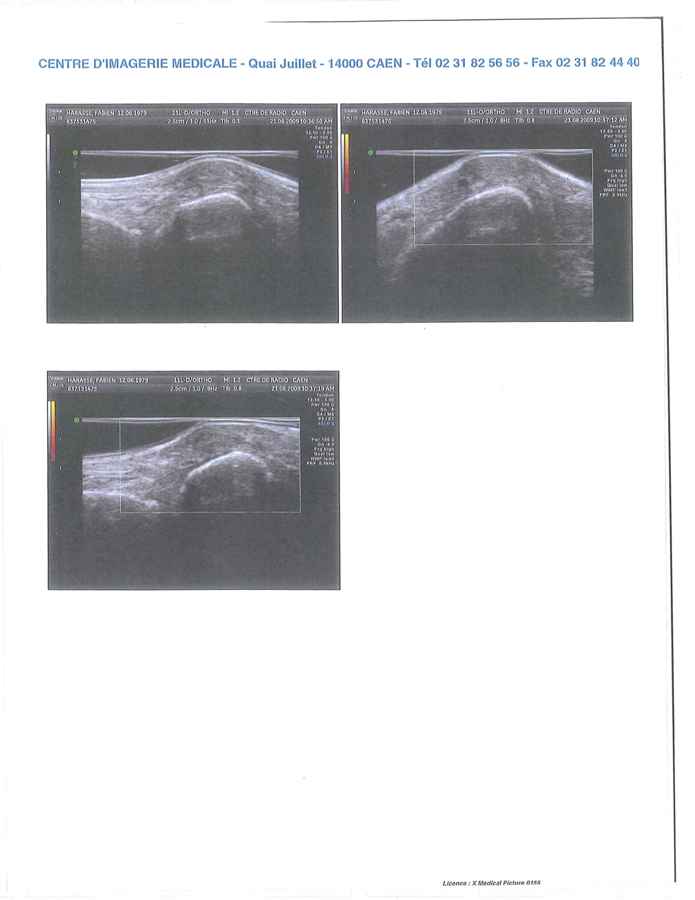

Après différents examens (radio et écho), il a été mis en évidence que la bosse au niveau de mon Scaphoïde gauche (voir photos) est dut à un échauffement du pied au contact de la zone d’ancrage de la bride supérieure. Cet échauffement se répète à chaque coupe de pied.